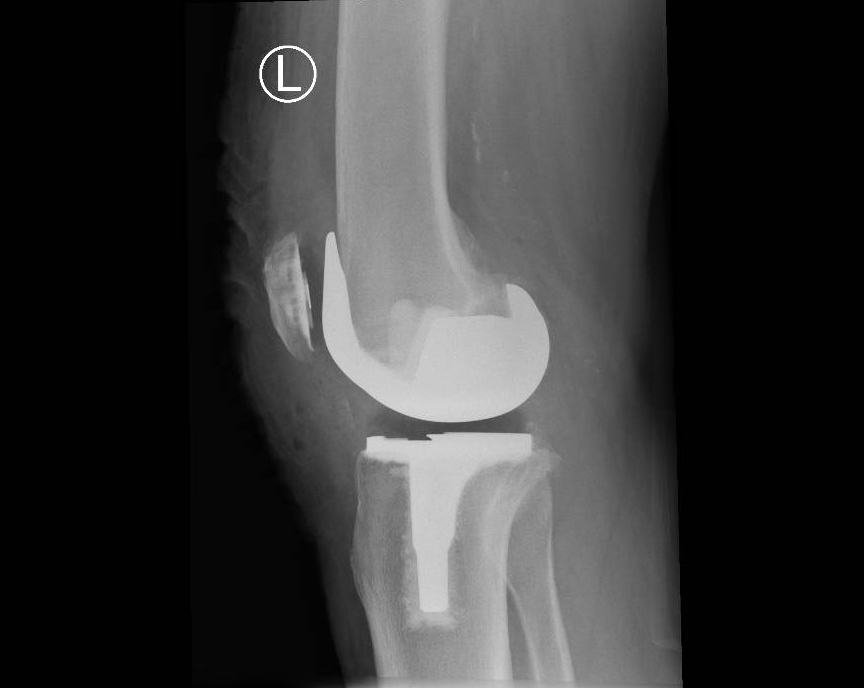

Total Knee Replacement

When more than one compartment (medial, lateral, patella) of the knee wears out and non-operative treatment options have failed a total knee replacement is required.

If the arthritis within the knee affects more than one compartment then a total knee replacement may be recommended.

In a conventional knee replacement, instruments are used to perform the bony cuts and restore the knee back to its original (mechanical) position. This involves releasing some of the ligaments and soft tissues around the knee so that a balanced, full range of motion is achieved at the end of the surgery.

Through a midline incision the surfaces of the bone can be replaced. The femoral component is a smooth metal component of varying sizes, which fits over the end of the femur. The tibial component consists of a metal base plate that sits on top of the tibia and a polyethelene (plastic) insert that fixes onto the tibial component. The patella surface may be replaced if it is worn. The implants are positioned and fixed to the bone using bone cement.